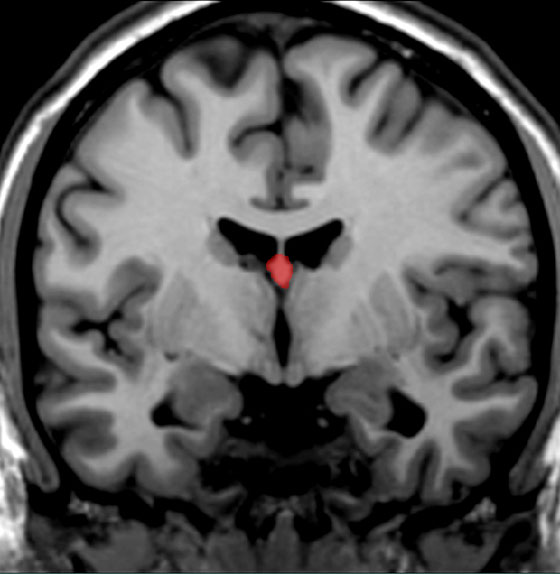

Locate one structure clearly visible in this scan in which the fornix terminates.